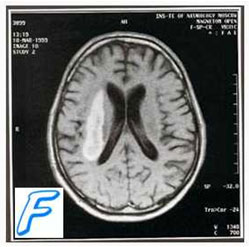

К достоверным методам диагностики геморрагического инсульта относятся исследование ликвора (примесь крови подтверждает геморрагический инсульт), КТ, церебральная ангиография.

В большинстве случаев, по мере увеличения внутриполушарных гематом, происходит их прорыв в желудочковую систему или субарахноидальное пространство.

Патогенез геморрагического инсульта. Стойкая, длительная артериальная гипертензия способствует морфологической перестройке стенки артериальных сосудов, конечным этапом которой является формирование фибриноидно-гиалинового некроза. При его наличии возможно образование расслаивающих аневризм, разрыв которых является причиной кровоизлияния в мозг. Как правило, образующаяся внутричерепная гематома начинает постепенно сдавливать окружающие отделы и вызывает перифокальный отек.